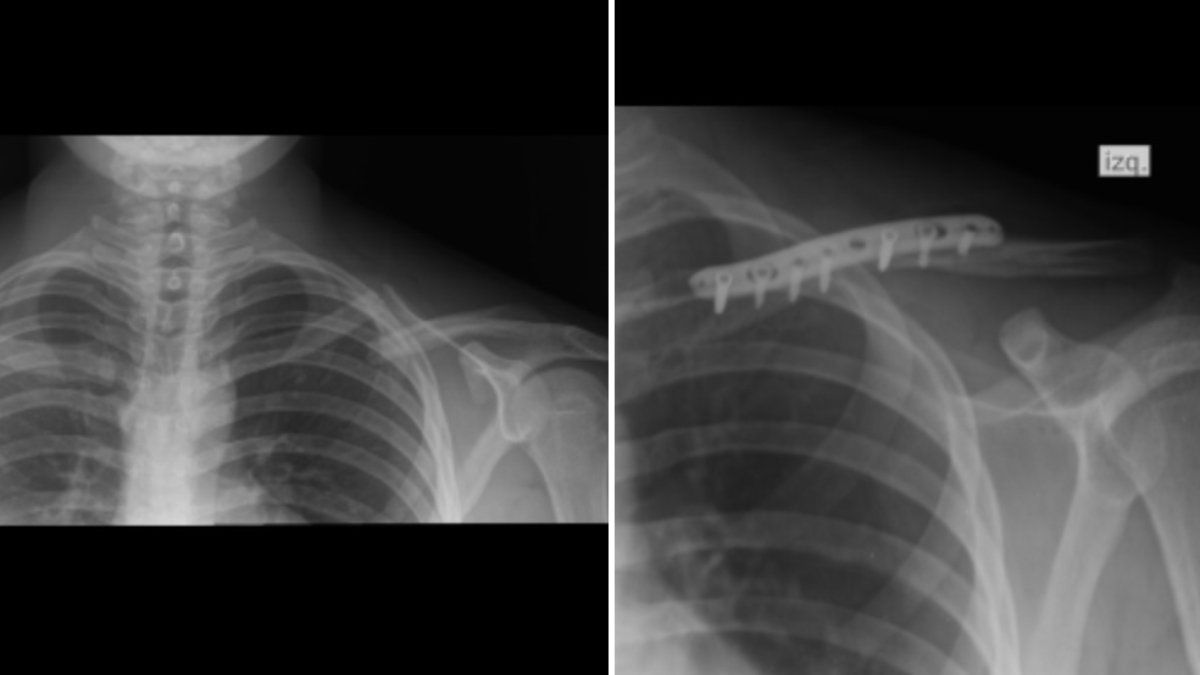

El joven terminó internado en una clínica donde le diagnosticaron fractura de tercio medio en la clavícula y debieron operarlo para reparar la lesión ósea. Todo quedó constatado en la causa judicial con distintos informes médicos.